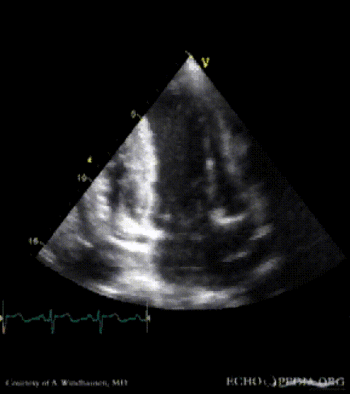

Severe Hypertrophic Cardiomyopathy (HCM)

Case description: Severe Hypertrophic Cardiomyopathy (HCM)

Courtesy of: A. Windhausen, AMC, The Netherlands

A2CH view A4CH view